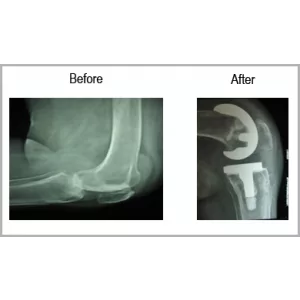

A female aged 65 years who is known case of Rheumatoid arthritis and on treatment since 4-5 years. She had severe left knee pain with swelling. She can’t bend her left knee.

She had left total knee replacement. No pain and normal walking.